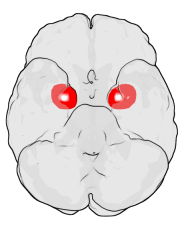

Location of the amygdalae in the human brain

Human brain in the coronal orientation. Amygdalae are shown in dark red.

The amygdalae (singular: amygdala; /əˈmɪɡdələ/; also corpus amygdaloideum; Latin, from Greek ἀμυγδαλή, amygdalē, 'almond', 'tonsil'[1]) are two almond-shaped groups of nuclei located deep and medially within the temporal lobes of the brain in complex vertebrates, including humans.[2] Shown in research to perform a primary role in the processing of memory, decision-making, and emotional reactions, the amygdalae are considered part of the limbic system.[3]